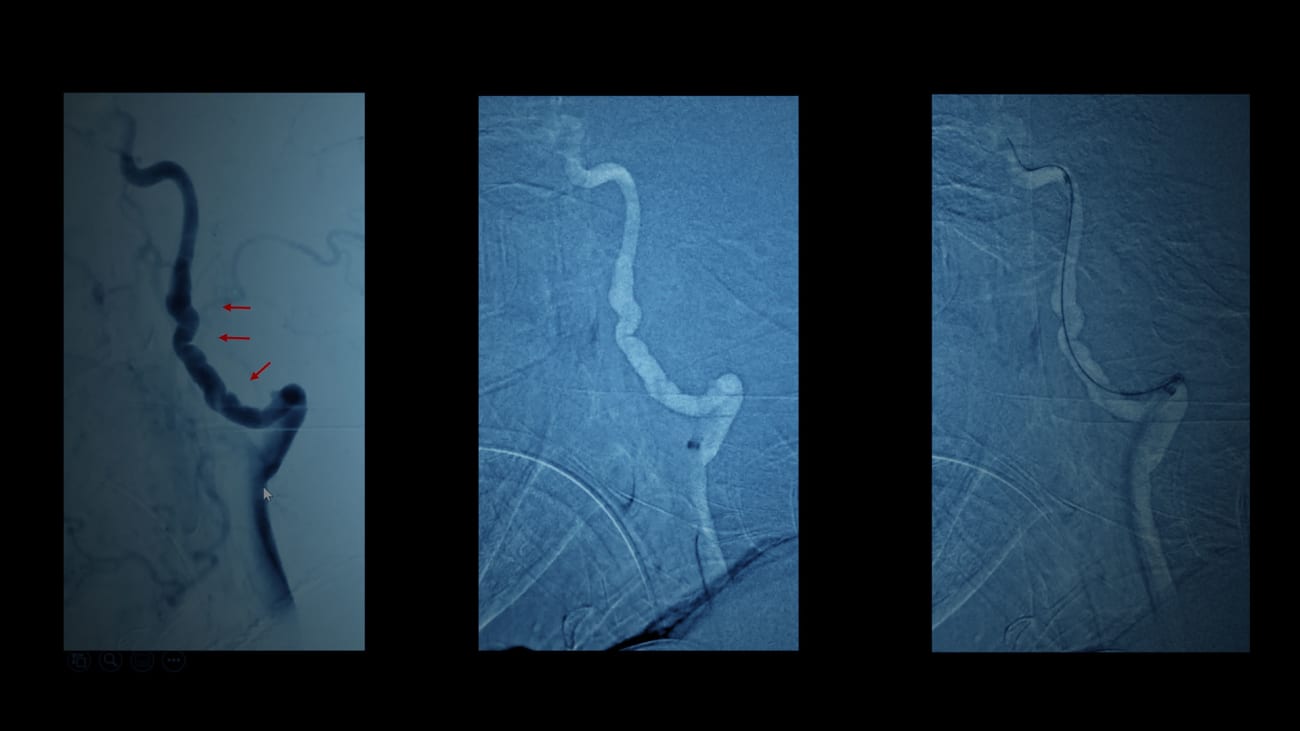

An 85-year-old female with a high-risk vascular anatomy from diffuse fibromuscular dysplasia presents at Mount Sinai Queens with disabling neurological deficits from emergent large vessel occlusion ischemic stroke. She undergoes endovascular thrombectomy, and 48 hours later is discharged home without any residual neurological deficit or need for physical therapy.

Shahram Majidi, MD, Assistant Professor of Neurosurgery, Diagnostic, Molecular and Interventional Radiology, and Neurology, who led the surgery, narrates the patient case with tips for successful thrombectomy.